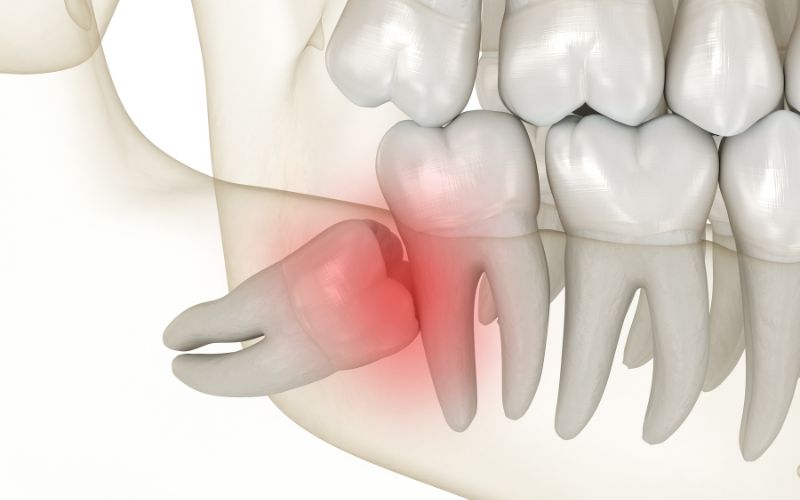

Trong quá trình phát triển của con người, răng khôn mọc lệch là một hiện tượng phổ biến nhưng thường bị xem nhẹ cho đến khi cơn đau răng khôn xuất hiện. Khác với các răng khác, răng khôn thường mọc ở vị trí cuối cùng trong cung hàm – nơi không còn đủ khoảng trống, dẫn đến tình trạng mọc lệch, mọc ngầm hoặc đâm vào răng kế cận. Khi không được xử lý sớm, nó có thể gây viêm nướu, sâu răng lân cận, thậm chí tổn thương xương hàm.

Sự sai lệch này dẫn đến áp lực bất thường trong quá trình mọc răng, khiến răng khôn đâm vào răng số 7 hoặc mọc ngầm trong xương. Nếu không phát hiện sớm, nó có thể gây đau răng khôn, viêm nướu và tiêu xương cục bộ. Việc chẩn đoán hình thể xương hàm bằng phim X-quang toàn cảnh giúp bác sĩ xác định chính xác hướng mọc để lên kế hoạch điều trị răng khôn mọc lệch phù hợp.

Ngoài ra, răng khôn mọc ngầm sâu trong xương có thể tạo nang chân răng, tiêu xương ổ hoặc làm xô lệch toàn bộ khớp cắn. Trong trường hợp này, điều trị răng khôn mọc lệch cần phối hợp chẩn đoán hình ảnh và phẫu thuật chính xác để tránh tổn thương dây thần kinh và mô quanh răng.